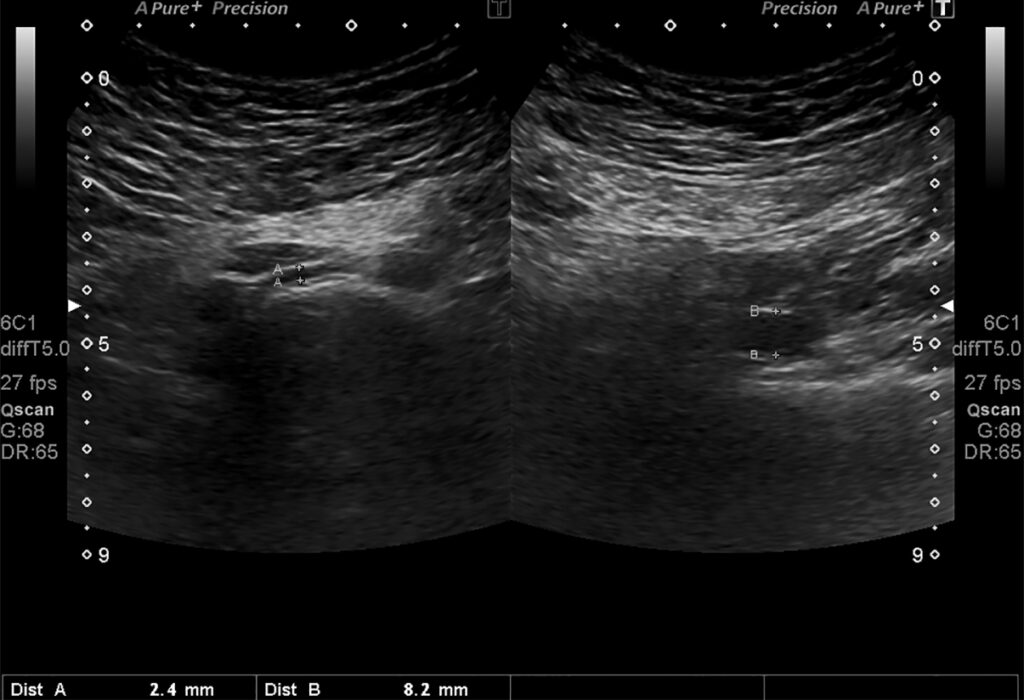

Fig. 6. Ecografía transabdominal: la VICI antes de pasar entre la AICD y la columna mide 2.4 mm; dilatación distal de 8.2 mm.

Hallazgos imagenológicos. En el eco Doppler ginecológico por vía transvaginal se observa varicocele pelviano (Fig. 5). En el eco Doppler abdominal se visualiza vena iliaca común izquierda (VICI), la que mide 2.4 mm antes de pasar entre a la arteria iliaca común derecha (AICD) y la columna y 8.2 mm en el segmento distal (Fig. 6). Estudio que corresponde en primera instancia a síndrome de May Thurner.